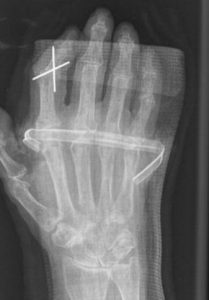

O tratamento está limitado à fixação cirúrgica da articulação (Artrodese). Estas artrodese podem ser feitas de várias formas.

Figuras 30 e 31: Luxação IF; artrodese articular